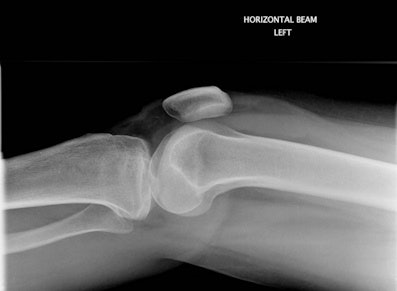

Figure 1A: False-negative outcome after a knee radiograph. The patient within the standard delayed reporting arm was discharged by the accident and emergency (A&E) clinician as normal for further A&E review if required. All images courtesy of Maryann Hardy, PhD.